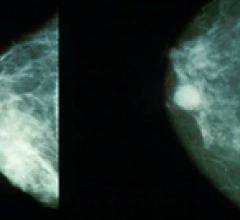

Despite decades of progress in breast imaging, one challenge continues to test even the most skilled radiologists ...

Breast imaging centers, like many other users of imaging systems, are jumping feet-first into digital technology. The ...